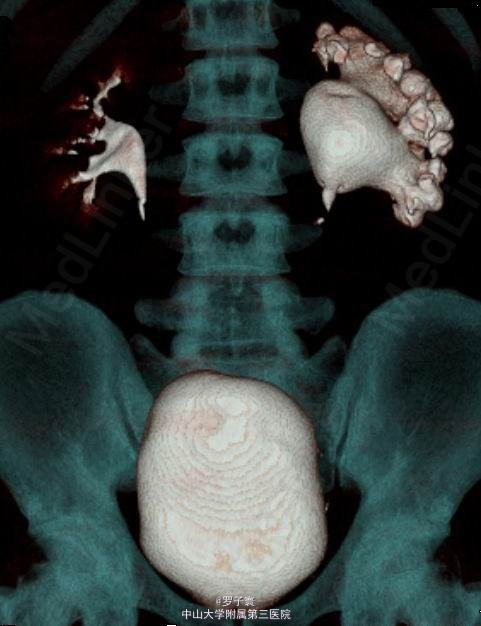

体格检查:体温38.7oC,心率90次/min,呼吸19次/min,血压110/80mmHg,皮肤黏膜、巩膜无黄染,全身浅表淋巴结无肿大,心肺未见异常,双肾区无红肿、隆起,压痛(-),反跳痛(-)。左肾区叩击痛(+),左肾肋脊点,肋腰点压痛(-),右侧肋脊点、肋腰点压痛(-)。腹平软,左侧输尿管走行区无明显压痛,右侧输尿管走行区压痛(-),膀胱区无膨隆,压痛阴性,双侧腹股沟区未触及肿物。辅助检查:大便常规,血生化,胸片,心电图均无明显异常。血常规:WBC11.5×109/L。尿常规:潜血(+),白细胞(+++),尿沉渣白细胞计数678.8个/μL,红细胞计数36.1个/μL。尿培养+药敏:头孢他啶、头孢吡肟、亚胺培南敏感。泌尿系彩超:考虑左侧肾盂输尿管移行处狭窄并左肾积水。中腹部CT平扫+增强+CTU:左侧肾盂输尿管移行区狭窄并左肾肾盂肾盏中度积水扩张(图1)。

入院后予复达欣抗感染治疗一周,患者感染控制良好。于2013-10-12日在全麻下行“腹腔镜下左侧肾盂输尿管成形术”。术中于输尿管切开处置入COOK 4.7F双J管一条,术后复查腹部平片提示:双J管于输尿管下段迂折,未抵达膀胱(图2)。于2013-10-15在腰硬联合麻醉下行“输尿管球囊扩张+逆行置管术”,术中发现输尿管口较正常成人较小,用9F输尿管镜进镜困难,更换小儿4.5F输尿管镜顺利进入,发现输尿管下段在壁内段以上的管腔仍很狭窄,内径约3mm,长度约2.5-3cm,双J管于狭窄最高处迂折,迂折处内径大约5-6mm,于4.5F输尿管镜直视下将留置超滑导丝,逆行将8mmX15cm输尿管球囊扩张器跨过狭窄段,将球囊扩张器水压升至25afm,维持10min,待扩张后直视下逆行放置双J管,术后复查平片双J管位置正常(图2)。术后予心电监护、吸氧、抑酸、抗感染、营养支持治疗。术后恢复良好,予以出院。出院诊断:1.左侧肾盂输尿管连接处梗阻并左肾积液2.左侧输尿管下段狭窄。